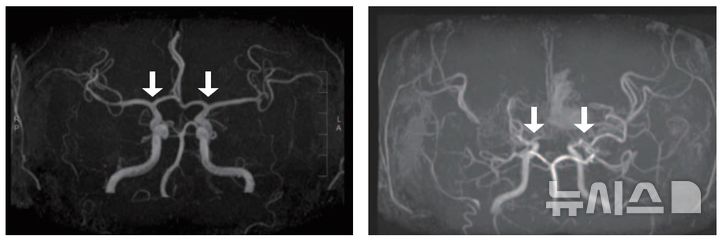

[서울=뉴시스] 정상(왼쪽) 및 모야모야병 환자의 뇌혈관. (사진= 서울대병원 제공)

모야모야병은 특별한 원인 없이 대뇌에 혈액을 공급하는 내경동맥의 혈관이 서서히 좁아지는 만성 진행성 뇌혈관질환이다. 이로 인해 혈류가 부족해 지고, 부족한 혈류를 보충하려는 비정상적인 미세혈관이 자라나지만, 이 혈관들은 충분한 혈액을 공급하지 못하고 터지기 쉬워 뇌경색 뇌출혈과 같은 심각한 소아 뇌졸중을 유발하게 된다.

기존에는 모야모야병을 확진하기 위해서는 침습적인 뇌혈관 조영술이 표준 검사였고, 이는 소아에게 큰 부담을 줬다. MRI(자기공명영상)·MRA(자기공명혈관조영술)과 같은 비침습적 검사도 있지만, 모야모야혈관을 자세하게 평가하기 어려워 조기 진단에는 한계가 있었다.